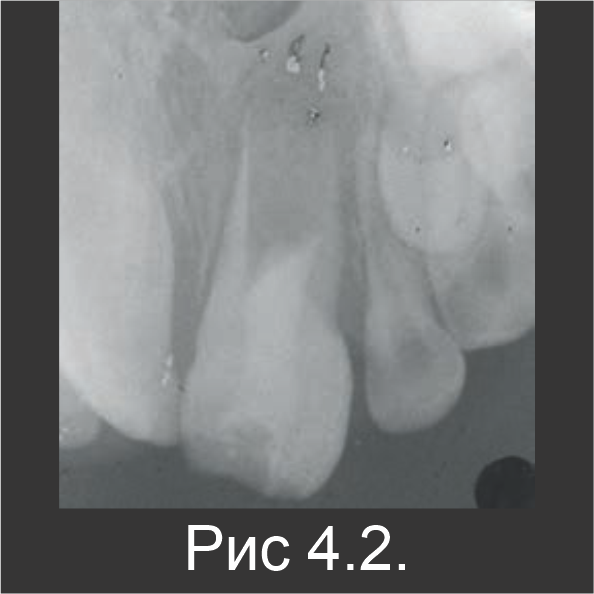

6-летнего мальчика направили на лечение абсцесса зуба № 21. За две недели до этого он перенес травму зуба. У него был диагностирован неосложненный перелом коронки зуба 21. У него была болезненная припухлость со щечной стороны от зуба 21, и во время пальпации из бороздки выделялся гной. При этом пульпа была закрыта. Зуб имел увеличенную подвижность и был чувствительным к перкуссии. При контакте с холодовым раздражителем реакции не наблюдалось, что позволило предположить полный некроз пульпы. На рентгенограмме был обнаружен совсем незрелый резец 21 с просветлением в области апекса, которое имеет большое значение (рис. 4.1).

После инъекции местного анестетика, зуб 21 открыли, и выпустили гной. Канал тщательно промыли гипохлоритом натрия, чтобы удалить некротические ткани и остатки, после чего выполнили окончательное промывание физраствором. После просушивания канала, гидроокись кальция в пастообразной форме оставили на 3 недели, в непосредственном контакте с оставшейся тканью (рис. 4.2).